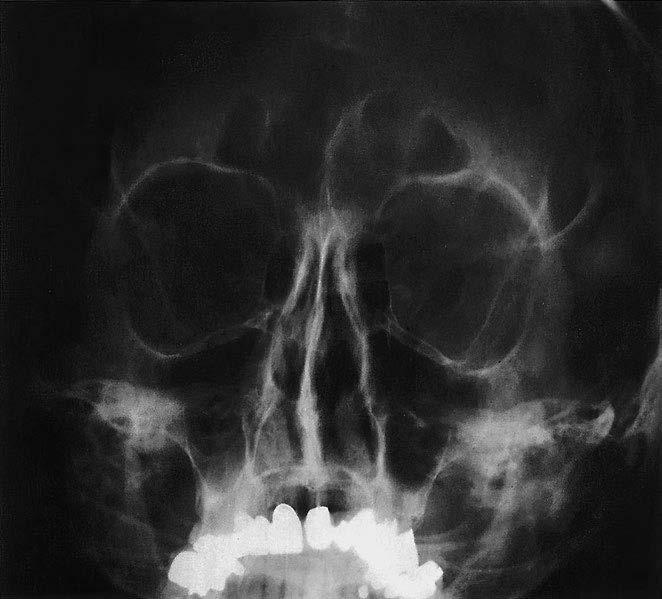

1 sinus frontalis (dutina kosti čelní)

2 os nasale (kost nosní)

3 přední etmoidální sklípky

4 orbita (očnice)

5 septum nasi (nosní přepážka)

6 ala major ossis sphenoidalis (velké křídlo kosti klínové)

7 foramen infraorbitale

8 foramen rotundum

9 zadní etmoidální sklípky

10 os zygomaticum (kost lícní)

19 mandibula (dolní čelist) Paranazální dutiny, okcipitomentální (Watersova) projekce

11 sinus maxillaris (dutina horní čelisti)

12 recessus alveolaris maxillae

13 sinus sphenoidalis (dutina kosti klínové)

14 foramen ovale

15 processus alveolaris maxillae

16 caput mandibulae (hlavice dolní čelisti)

17 margo superior partis petrosae (horní hrana pyramidy / kosti skalní)

18 lingua (jazyk)